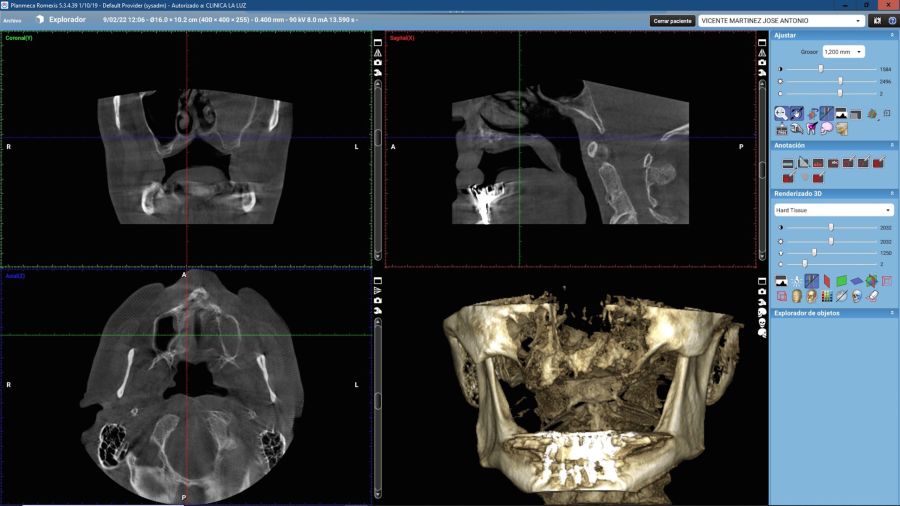

For this purpose, intraoral photographs were made and the complete prosthesis of the patient was used for the different planning tests. First, the double scanning technique was used, adding different radiopaque markers with gutta percha in the prosthesis10 (Figure 3). Then, the scanning was obtained with a conical beam computerized tomography (CBCT), (Planmeca ProMax 3D, Helsinki, Finland), both the prosthesis and the patient with his prosthesis stabilized with a silicone bite registration (Figure 4). In addition, an intraoral scan of the patient’s prosthesis was performed. From this, a personalized structure was designed subperiosteal sintered in Titanium (Ti-6-4) (Custom 3D®) with 6 Multi-Unit® type connections (Branemark, Nobel Biocare) and fixed with osteosynthesis screws in the higher density and volume areas of the malar bone and upper jaw (Figure 5 and 6). At the same time, with the STL digital test of the planning of the mesh, and with the scanning of our complete prosthesis, the laboratory technician made an implantosupported rehabilitation milled in polymethylmethacrylate (PMMA) with Multi-Unit® type titanium interfaces for immediate loading (figures 7 and 8).